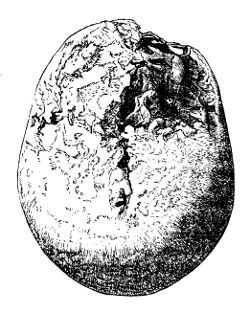

| InjuFractures of the Cranial Bones | 227 |

| Fracturesof the Cranium and Face | 558 |